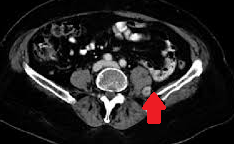

MRI of the retroperitoneum. Red arrow — metastatic lesion in the left psoas muscle (Courtesy Dr. V. Penopoulos).